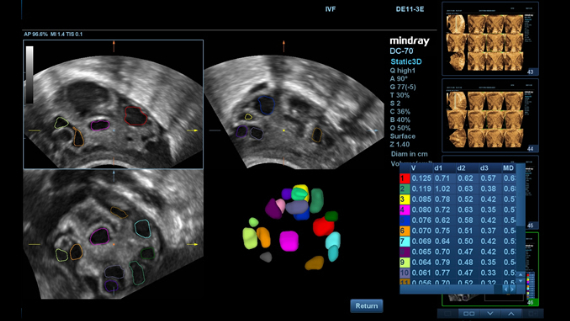

–°–Њ–≤–Љ–µ—Б—В–љ–Њ —Б —Б–Њ–≤—А–µ–Љ–µ–љ–љ—Л–Љ–Є —Г–ї—М—В—А–∞–Ј–≤—Г–Ї–Њ–≤—Л–Љ–Є —В–µ—Е–љ–Њ–ї–Њ–≥–Є—П–Љ–Є –љ–Њ–≤–Њ–µ —А–µ—И–µ–љ–Є–µ –Њ—В Mindray –њ—А–µ–Њ–±—А–∞–Ј—Г–µ—В –∞–Ї—В—Г–∞–ї—М–љ—Л–µ –Ј–∞–і–∞—З–Є –Ї–ї–Є–µ–љ—В–Њ–≤ –≤ –Ї–ї–Є–љ–Є—З–µ—Б–Ї–Є–µ –њ–Њ—В—А–µ–±–љ–Њ—Б—В–Є.

–°–Є—Б—В–µ–Љ–∞ DC-70 Exp —Б X-Insight –њ–Њ–Љ–Њ–≥–∞–µ—В —Г–њ—А–∞–≤–ї—П—В—М –њ–Њ–≤—Б–µ–і–љ–µ–≤–љ–Њ–є –Ї–ї–Є–љ–Є—З–µ—Б–Ї–Њ–є –њ—А–∞–Ї—В–Є–Ї–Њ–є —Б –ї–µ–≥–Ї–Њ—Б—В—М—О –Є —Г–≤–µ—А–µ–љ–љ–Њ—Б—В—М—О.

–Ю—Б–љ–Њ–≤—Л–≤–∞—П—Б—М –љ–∞ –≥–ї—Г–±–Њ–Ї–Њ–Љ –њ–Њ–љ–Є–Љ–∞–љ–Є–Є –њ–Њ—В—А–µ–±–љ–Њ—Б—В–µ–є –Ї–ї–Є–µ–љ—В–Њ–≤, –Ї–Њ–Љ–њ–∞–љ–Є—П Mindray —А–∞–Ј—А–∞–±–Њ—В–∞–ї–∞ —Б–Є—Б—В–µ–Љ—Г DC-70 Exp —Б X-Insight, —З—В–Њ–±—Л –Њ–±–µ—Б–њ–µ—З–Є—В—М eXpress Clarity, eXceptional Intelligence, eXceeding Experience.